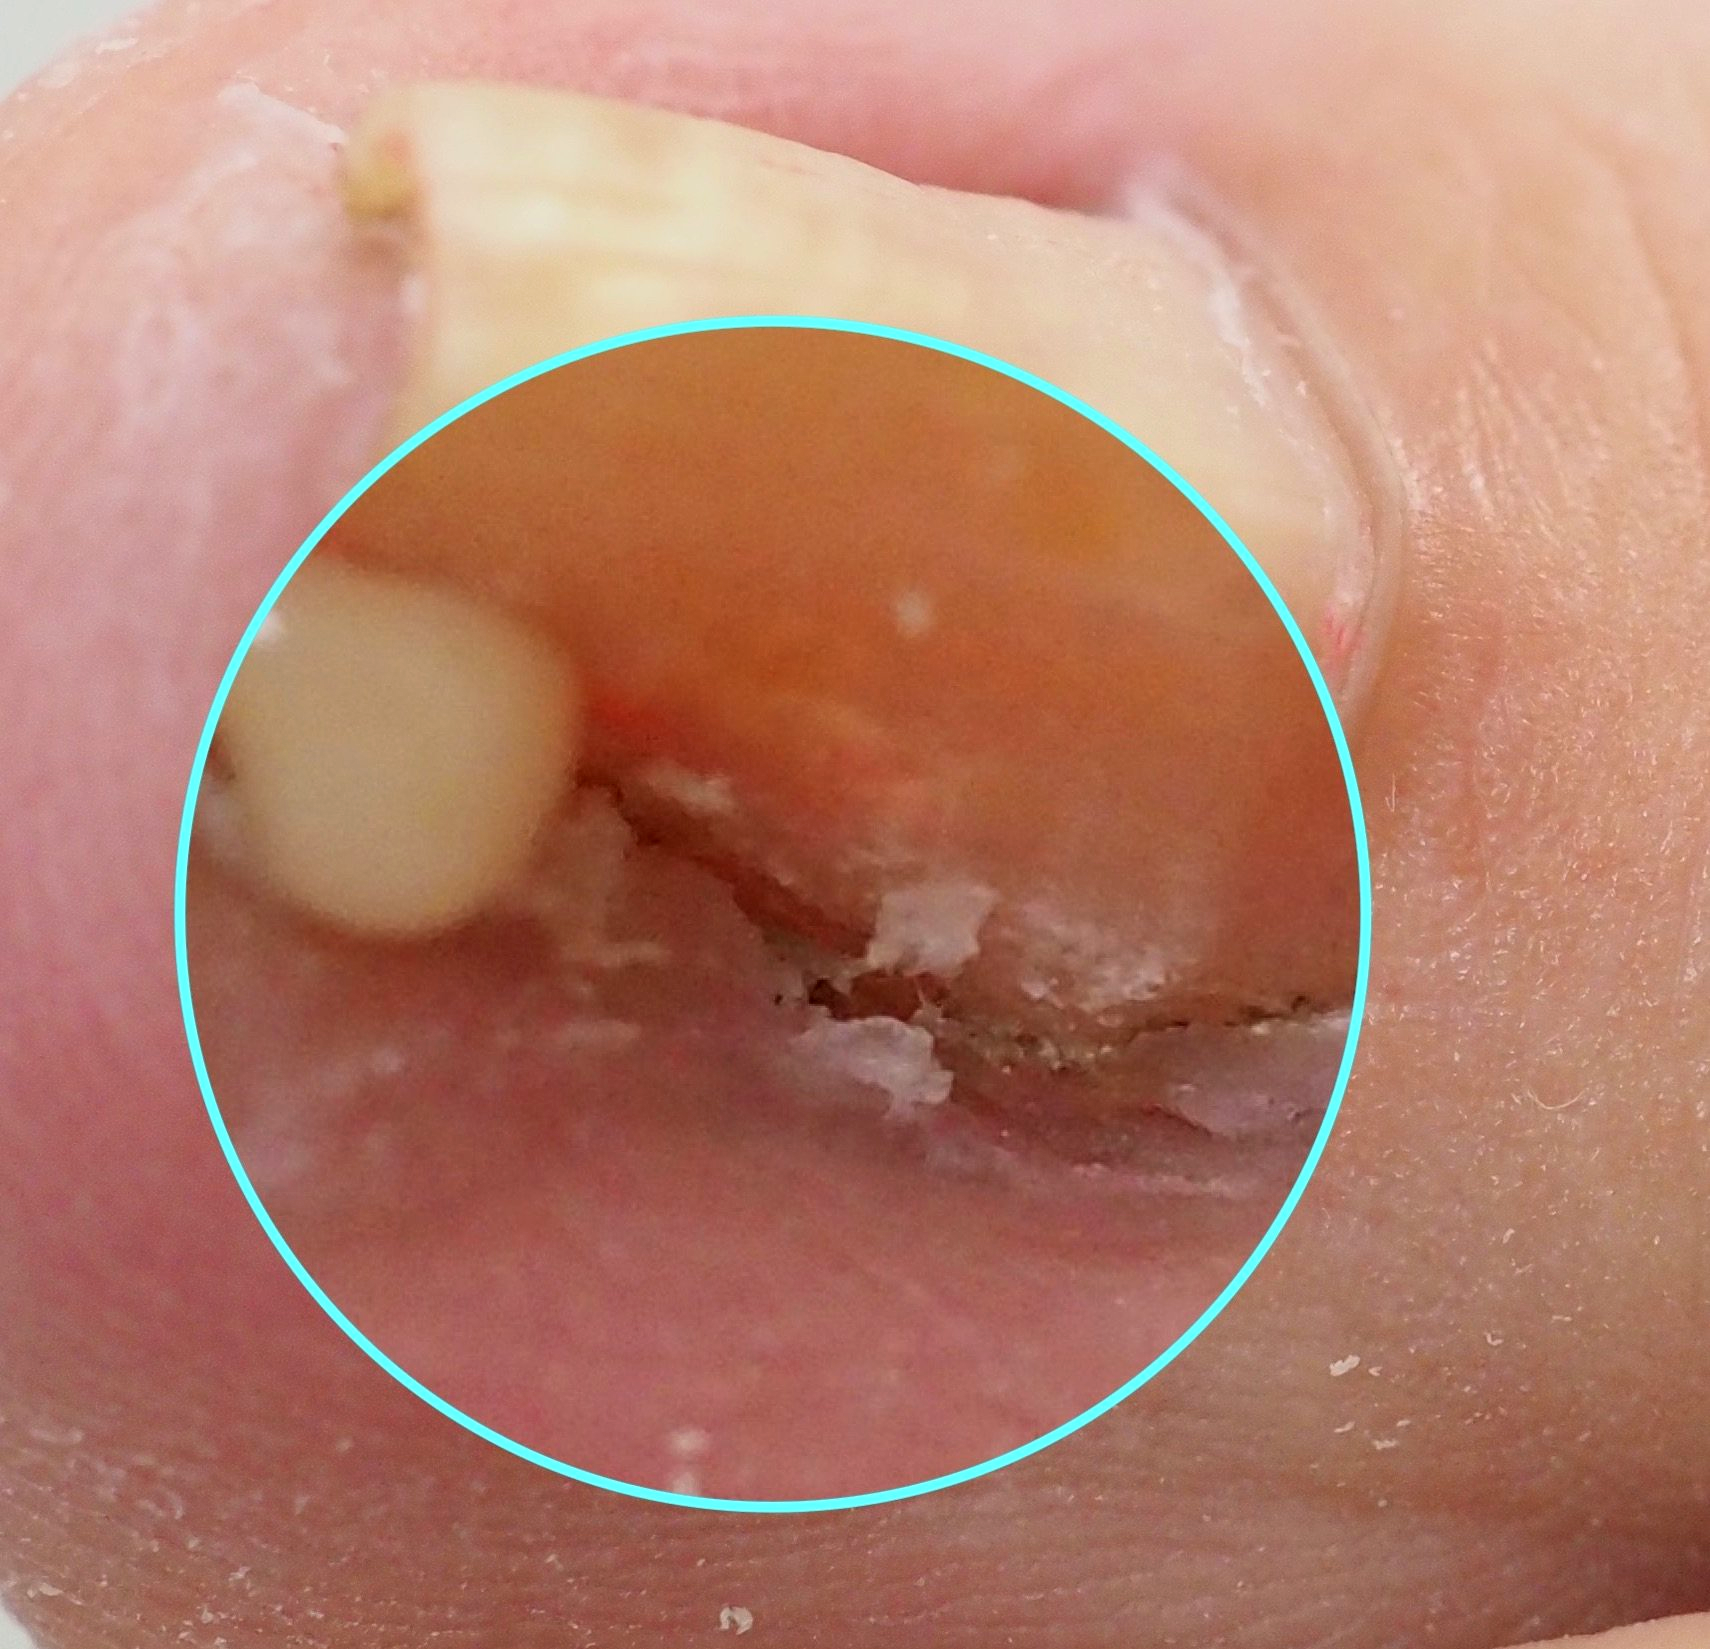

🔴Bild 3: der geborgene Nagelspan Bild 4: in dieser Position grub sich der Nagel durch das Gewebe